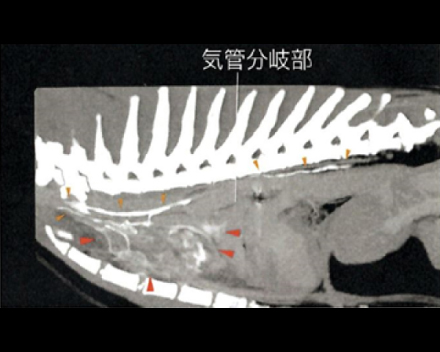

CT検査にて気管の圧迫を確認

内視鏡の位置をCアームで確認し正確に場所の把握が可能